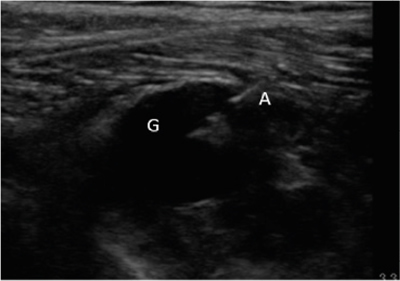

Neuropatía peronea secundaria a ganglión extraneural: revisión de literatura y propuesta de tratamiento. Caso no positivo

Peroneal neuropathy caused by an extraneural ganglion: literary review and treatment proposal. A non-positive case

Este artículo presenta el caso de un paciente de 69 años con una neuropatía compresiva peronea secundaria a un ganglión, inicialmente interpretada como una radiculopatía L5. Este incorrecto enfoque supuso la sobremedicación del paciente, un mal control algésico, la realización de una discectomía L4-L5 innecesaria y una pobre evolución neurológica.

Un enfoque diagnóstico correcto y un abordaje terapéutico precoz habrían supuesto una mayor mejoría clínica e incluso una recuperación neurológica completa del paciente. Por ello, este caso sirve para resaltar: a) el valor de la ecografía en neuropatías periféricas como herramienta diagnóstica y pronóstica y el de la ecografía en gangliones como arma diagnóstico-terapéutica; b) el uso de las pruebas diagnósticas como apoyo a una exploración física exhaustiva, y no como diagnóstico en sí mismas, y c) la importancia de la publicación de casos no positivos para optimizar recursos, evitar repetir errores, reducir el sesgo de publicación y facilitar el inicio de proyectos de investigación.

Figura 2